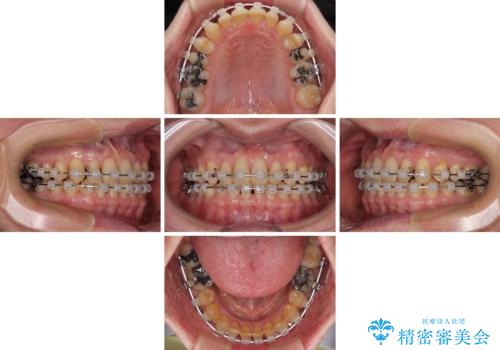

【モニター】ディープバイトで隙間の空いた歯列 ワイヤー装置での非抜歯矯正

- 前歯のデコボコと隙間の空いた歯列を気にして来院された患者様です。

下顎前歯が隠れるほどのディープバイトにより、強い咬合力と突き上げで上顎歯列に隙間が空いている状態でした。

手前に傾斜している奥歯をワイヤー装置で立ち上がらせ、咬み合わせの高さを挙上することで突き上げを解消し、空隙歯列を改善していくこととしました。

ディープバイトが改善され、睡眠時の食いしばりも緩和され、顎への負担が軽減されました。